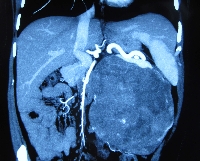

Πρόκειται για γυναίκα ασθενή 43 ετών, η οποία υποβλήθηκε σε υπερηχογράφημα άνω κοιλίας στα πλαίσια διερεύνησης άτυπων γαστρεντερικών συμπτωμάτων (αίσθημα κορεσμού και τάση προς έμετο). Διαπιστώθηκε η ύπαρξη ευμέγεθους μάζας της παγκρεατικής ουράς, διαμέτρου 22 cm, με κυστικά και συμπαγή στοιχεία. Η αξονική τομογραφία επιβεβαίωσε τα υπερηχογραφικά ευρήματα (εικόνα 1) και επιπλέον ανέδειξε το γεγονός ότι η μάζα εκτείνονταν ως το σπλήνα, ενέπλεκε το στόμαχο, τον αριστερό νεφρό, το μεσεντέριο και το παχύ έντερο και ότι έφτανε ως τα οστά της πυέλου (εικόνα 2). Εγχειρητικά, ύστερα από πολύωρη παρασκευή, η μάζα αποκολήθηκε en block από όλες τις προαναφερόμενες ανατομικές δομές (εικόνα 3) και, ύστερα από διαίρεση του παγκρεατικού παρεγχύματος στο επίπεδο του αυχένα του οργάνου, απομακρύνθηκε από το χειρουργικό πεδίο μαζί με το σπλήνα (εικόνα 4). Η ιστοπαθολογική εκτίμηση του παρασκευάσματος (εικόνα 5) ανέδειξε συμπαγή ψευδοθηλώδη όγκο, χωρίς στοιχεία κακοήθειας. Η άμεση μετεγχειρητική πορεία ήταν ανεπίπλεκτη, χωρίς την ανάπτυξη ενδοκοιλιακών συλλογών (εικόνα 6). Η ασθενής έλαβε εξιτήριο την 8η μετεγχειρητική ημέρα.